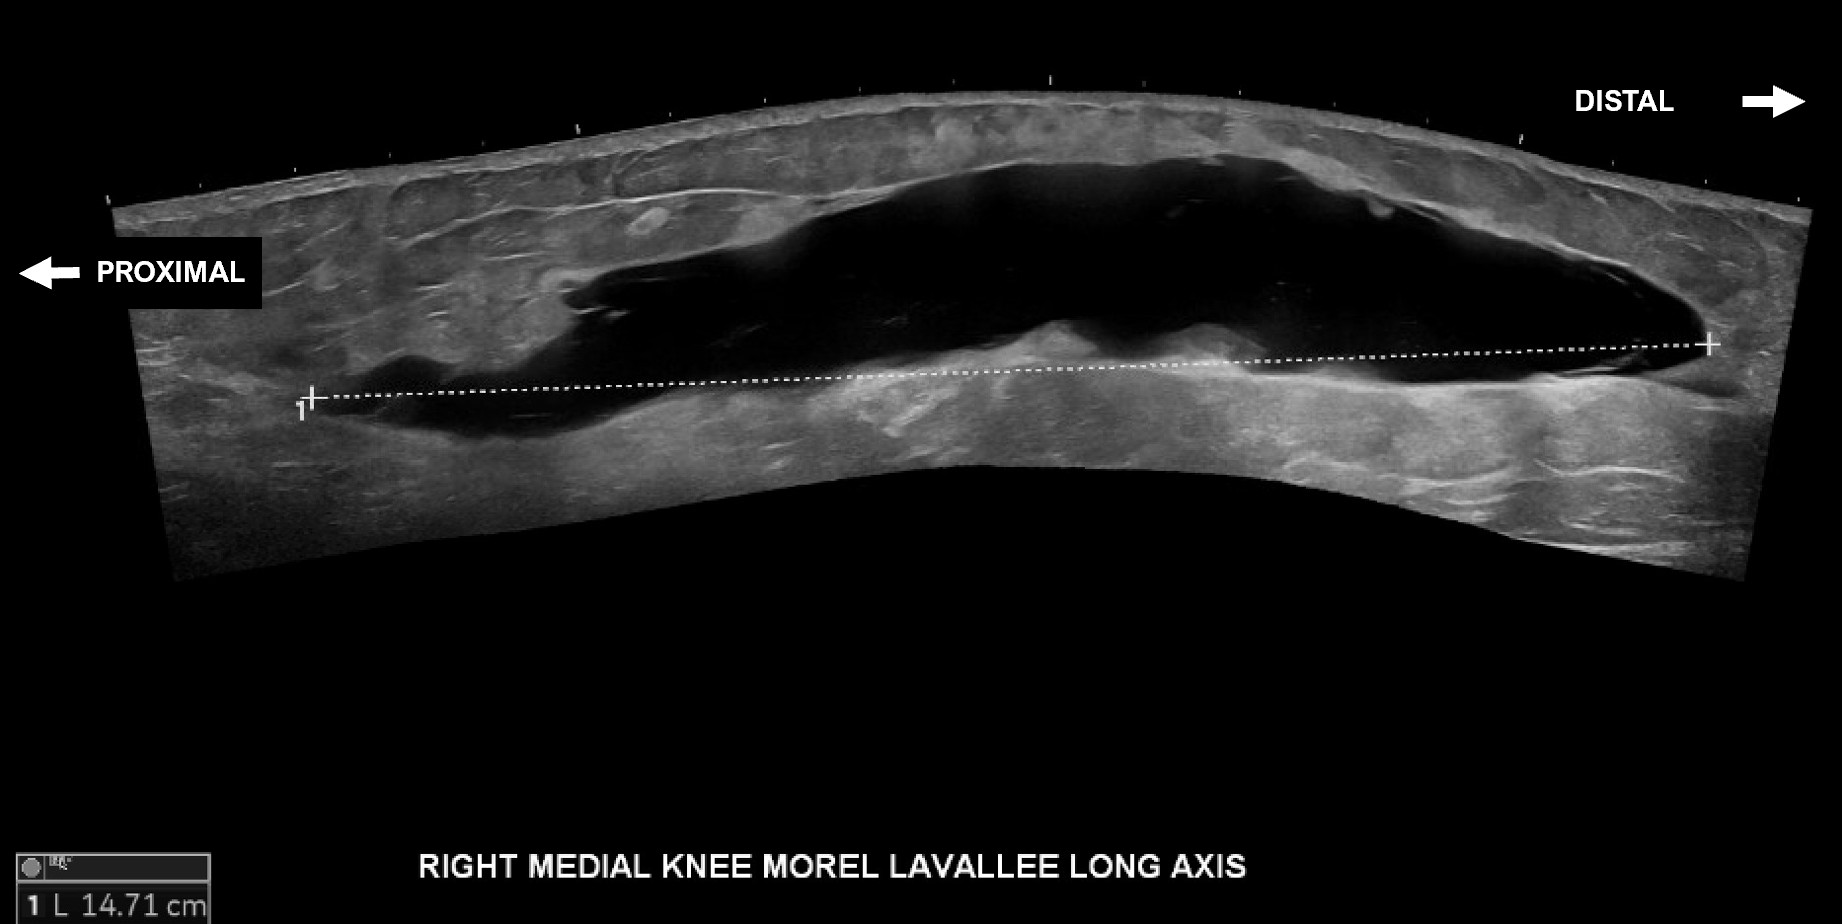

Unlabeled long axis extended view of the medial distal thigh and knee with evidence of a Morel-Lavallee lesion measuring approximately 14.7 cm from proximal to distal.

Labeled long axis extended view of the medial distal thigh and knee with evidence of a Morel-Lavallee lesion between the skin and superficial fat and the fascia and deep fat measuring approximately 14.7 cm from proximal to distal.